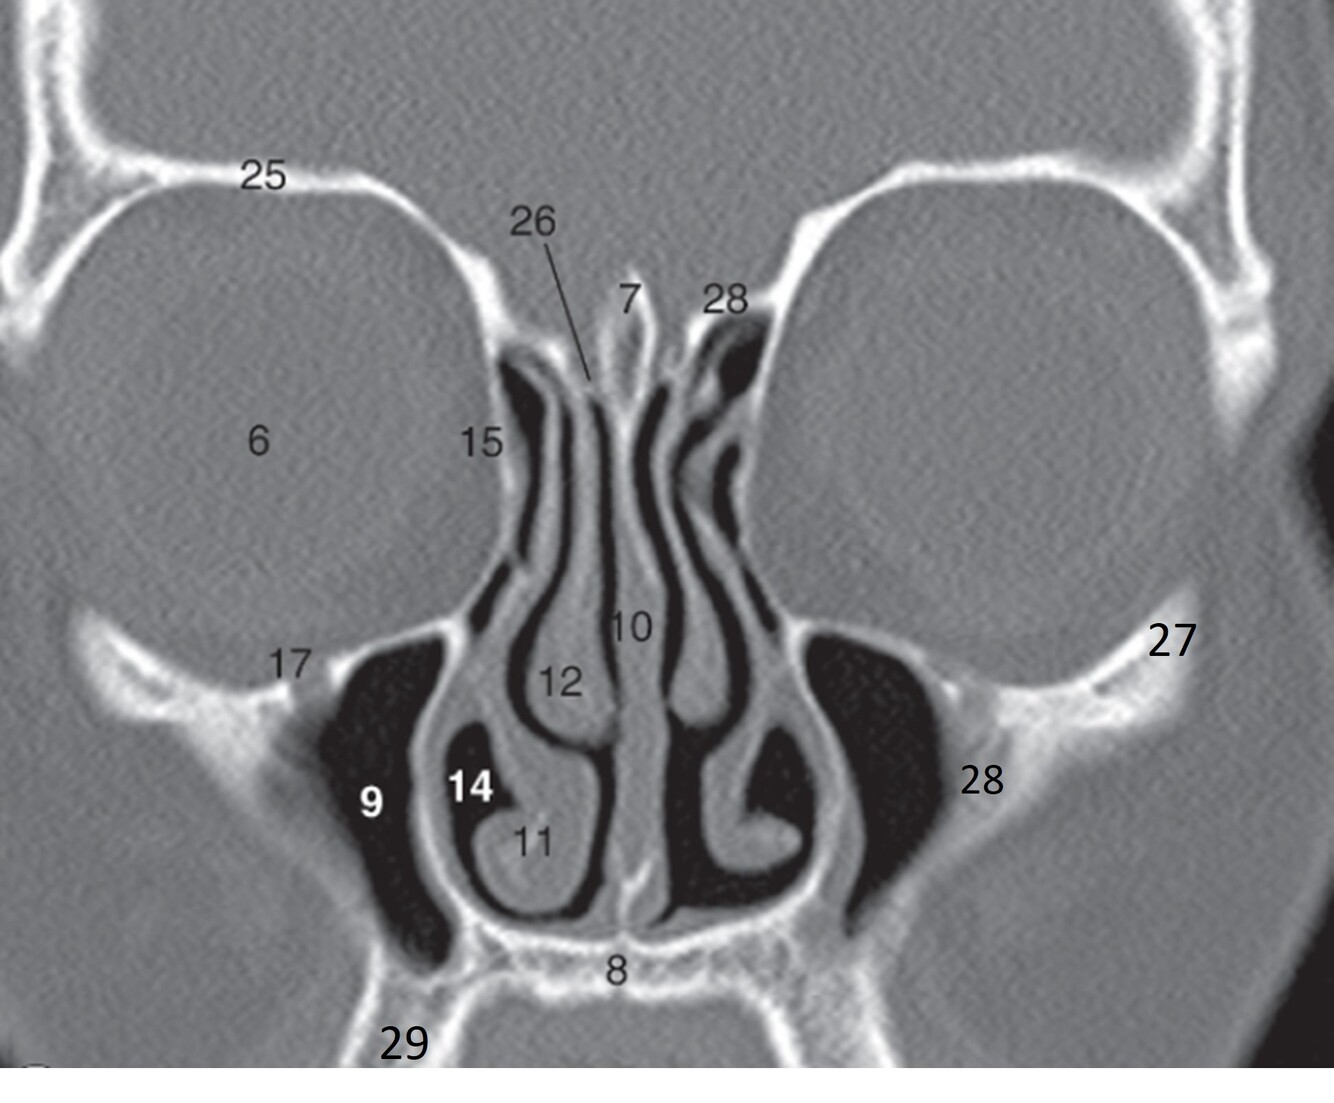

6

Label 7-12

7=Crista Galli (Ethmoid)

8.=Hard palate (Maxilla)

9=Rt. Maxillary sinus

10=Nasal septum

11=Rt. Inferior nasal concha

12=Rt. Middle nasal concha

7

Label 14,15,17,25,26

14=Rt. Inferior nasal meatus

15=Rt. Lamina papyracea (Ethmoid)

17=Rt infraorbital foramen (Maxilla)

25=Rt Orbital roof (frontal bone)

26=Rt Cribriform plate (Ethmoid)

8

Label 27-29

27=Lt Zygoma

28=Zygomatic process (Lt Maxilla)

29=Alveolar process (Rt Maxilla)

9

Label 8,9,10,12,13,18

8=Hard palate (Maxilla)

9=Lt maxillary sinus

12= Rt. Middle nasal concha

13=Rt. Superior nasal concha

18=Rt. Ethmoid air cells

Perfectly

Q

A

20-Lt. Superior nasal meatus

22=Rt maxilla (zygomatic process)

23=Rt zygoma

24=Lateral wall of Rt maxillary sinus

27=Perpendicular plate (ethmoid)

30=Rt. Lateral orbital wall (zygoma)

31=Rt. Orbital floor (maxilla)